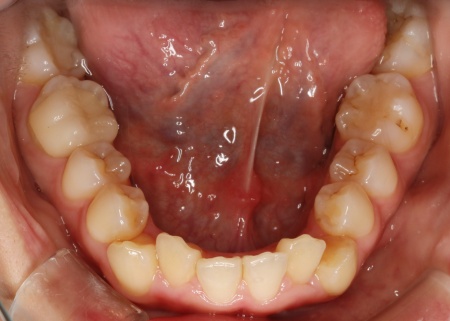

拝見したところ、上下の歯が正しく並ぶためのスペースが足りず、デコボコに生えていました。

とくに、犬歯が正しい歯並びから大きく飛び出した位置に生えており、いわゆる八重歯の状態です。

また、奥歯を噛み合わせた際に上下前歯が噛み合わず隙間ができる開咬(かいこう)も認められました。